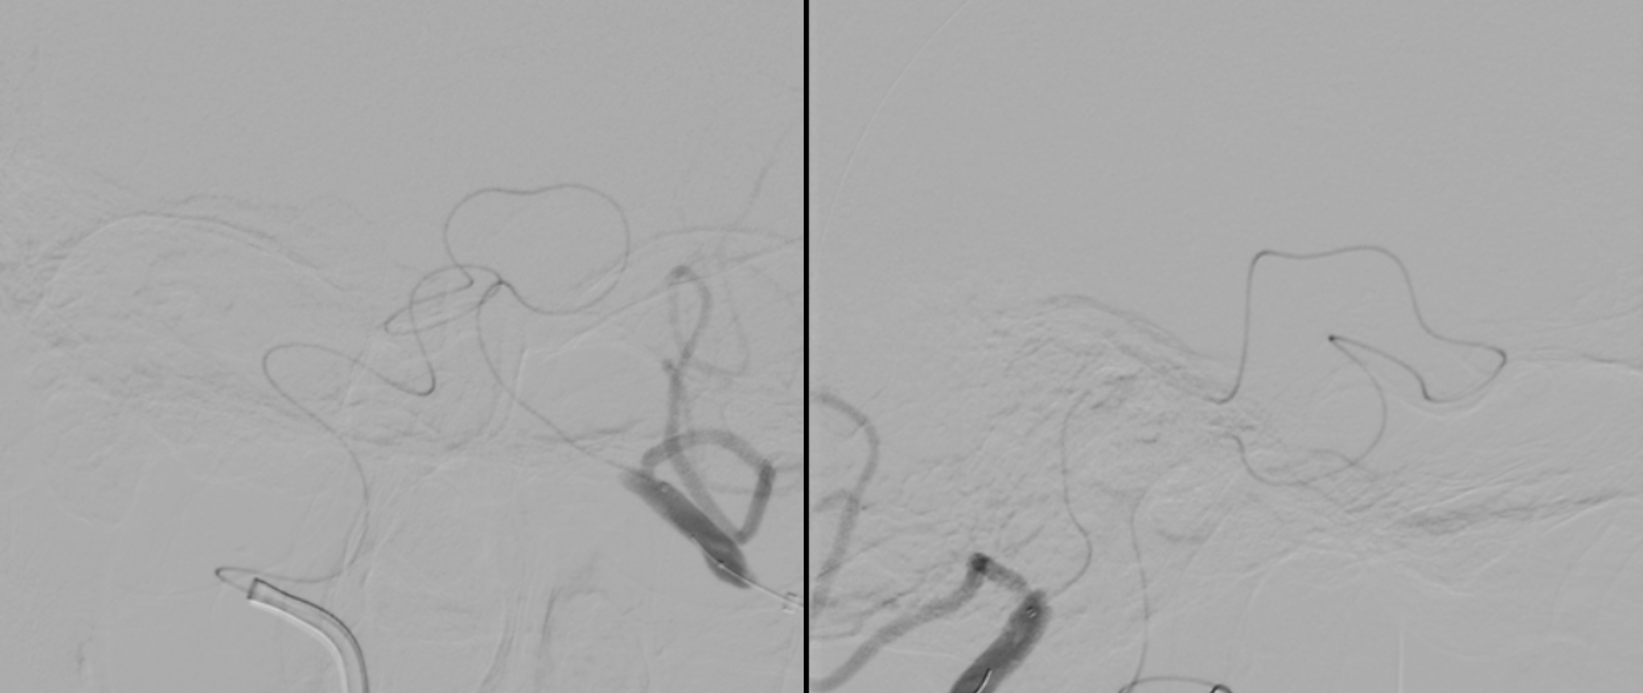

First angio

Small right PCOM

Unsuccessful Recan attempt